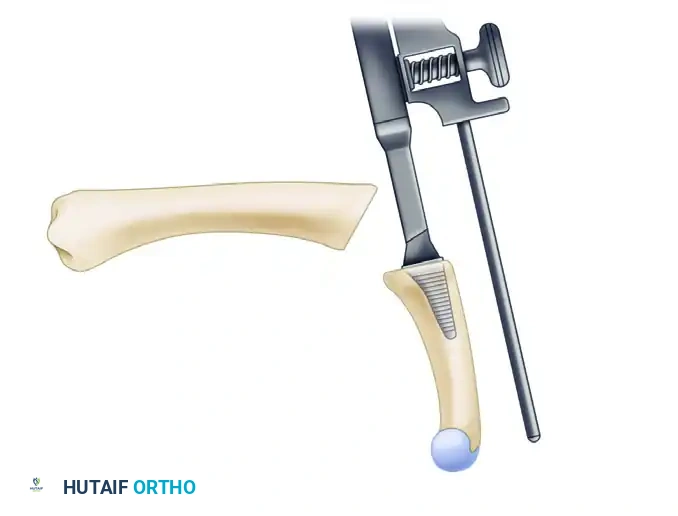

- Metacarpal Tunnel: Create an extraarticular bone tunnel from the dorsal base of the metacarpal to the volar beak apex.

- Vector: The tunnel must be in a plane strictly perpendicular to the thumb nail.

- Starting Point: Start just distal to the dorsal base of the metacarpal, between the extensor pollicis brevis (EPB) and extensor pollicis longus (EPL) tendons.

- Exit Point: The volar beak of the metacarpal. Do not breach the articular surface.

Figure: Gouge tract created in the sagittal diameter of the metacarpal, emerging at its volar beak. A small branch of the radial nerve is retracted volarly.

Intraoperative view demonstrating the creation of the metacarpal tunnel.